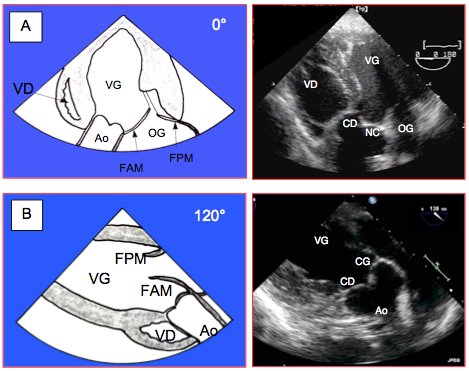

- Structure aortique fibreuse en forme de couronne à 3 branches verticales remontant aux commissures des cuspides. Elle définit 3 triangles fibreux intervalvulaires dans la paroi des sinus de Valsalva, qui sont le système de sustentation des cuspides. Les valves aortique et mitrale sont contiguës: la base du feuillet mitral antérieur est insérée sur le trigone fibreux en face des feuillets aortiques gauche et non-coronaire (Figure 26.67).

Figure 26.66 : Valve aortique ouverte in situ. Les 3 cuspides sont insérées en "U" dans la racine aortique; elles sont suspendues au niveau de la jonction sino-aortique et sont articulées comme une charnière au nadir de leur insertion (points bleus) ; ces 3 points sont situés sur l’anneau basal virtuel (traitillé bleu), qui est anatomiquement dans la chambre de chasse du VG, en-dessous de la jonction entre l’aorte et le VG. C’est l’endroit le plus rétréci de l’ensemble CCVG-racine aortique ; c’est aussi la structure que l’on mesure à l’écho comme anneau aortique, mais cette "structure" n'a pas de corrélat anatomique. Les 3 points commissuraux (points violets) sont situées sur la jonction sino-tubulaire. FAM : feuillet antérieur de la valve mitrale. MPA : muscle papillaire antérieur. MPP : muscle papillaire postérieur.

Figure 26.67: Représentation schématique de la racine aortique. Les 3 cuspides sont insérées en "U" dans la racine aortique (trait noir), au niveau des sinus de Valsalva ; elles sont suspendues au niveau de la jonction sino-tubulaire (pointillé rouge) et sont articulées par une charnière au nadir de leur insertion (points bleus) ; ces 3 points sont situés sur l’anneau basal (pointillé bleu), qui est en fait dans la chambre de chasse du VG, en-dessous de la jonction entre l’aorte et le VG (pointillé vert). Cet anneau basal, anatomiquement virtuel, est l’endroit le plus étroit du système CCVG - racine aortique - aorte ascendante ; par convention, c’est l’endroit où se mesure le diamètre de l’"anneau" aortique. Sa forme n’est pas circulaire mais légèrement elliptique. Les 3 points commissuraux (points violets) sont situées sur la jonction sino-tubulaire ; ils sont évasés de 5-10% par rapport aux points de l’anneau basal. *: triangles fibreux de la paroi des sinus de Valsalva qui sustentent les cuspides. En cartouche, représentation de la structure fibreuse qui soutient la valve aortique; elle a la forme d'une couronne à trois branches. Flèches rouges: trigones. FAM; feuillet antérieur de la valve mitrale.

La cuspide non-coronaire (NC) est la plus postérieure ; elle est située en regard du septum interauriculaire. La cuspide coronaire droite (CD) est la plus antérieure ; la cuspide coronaire gauche (CG) surplombe la CCVG. Leur surface est légèrement asymétrique, la cuspide non-coronaire étant la plus grande : NC > CD > CG. La partie centrale des bords libres présente un renforcement fibreux (nodule d’Arantius) qui est une structure anatomique normale. Sur la face ventriculaire des cuspides, on peut trouver des dégénérescences fibreuses (excroissances de Lambl) sous forme de filaments fins et mobiles flottant dans le flux sanguin; elles sont présentes dans 0.9% de la population mais sont peu emboligènes (voir Figure 25.153) [6].